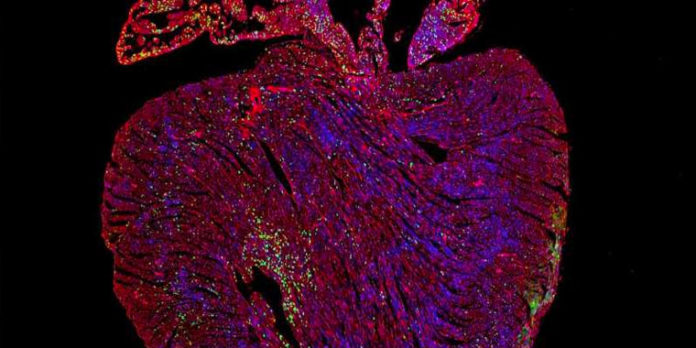

Cuando los investigadores hicieron que Myc fuera hiperactivo en un modelo de ratón, vieron sus efectos cancerosos en órganos como el hígado y los pulmones: una gran cantidad de células comenzaron a replicarse en el transcurso de unos días. Pero en el corazón, no pasó mucho.

Descubrieron que la actividad impulsada por Myc en las células del músculo cardíaco depende de manera crítica del nivel de otra proteína llamada Ciclina T1, producida por un gen llamado Ccnt1, dentro de las células. Cuando los genes Ccnt1 y Myc se expresan juntos, el corazón cambia a un estado regenerativo y sus células comienzan a replicarse. Los resultados se publican hoy en la revista Nature Communications.

«Cuando estos dos genes se sobreexpresaron juntos en las células del músculo cardíaco de ratones adultos, vimos una replicación celular extensa, lo que condujo a un gran aumento en la cantidad de células del músculo cardíaco», dijo Wilson.

Utilizando una tecnología de secuenciación de próxima generación llamada ChIP, los investigadores pudieron observar la acción de Myc en las células del corazón. Myc produce una proteína, llamada factor de transcripción, que se une al ADN en células específicas y activa la expresión génica. Pero a pesar de la unión de proteínas con éxito, las células del corazón no comenzaron a replicarse porque la proteína no podía activar la expresión génica. Otra proteína vital para la expresión génica, Cyclin T1, era deficiente en el corazón. Agregarlo a las células con el hiperactivo Myc causó que las células comenzaran a proliferar.